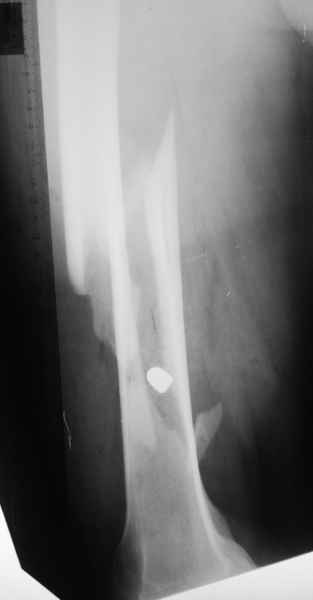

Больной 27 лет поступил 22.06.2010 по поводу огнестрельного пулевого слепого ранения

правого бедра на границе средней и нижней трети с огнестрельным косым оскольчатым переломом

правой бедренной кости со смещением отломков(снимок передняя проекция).Больной 110 кг

рост 176 см.Гемодинамически стабилен, показатели крови в норме. По передне-внутренней

поверхности правого бедра в средней трети имеется рана округлой формы диаметром 1 см.на

данный момент состояние удовлетворительное, признаков воспаления нет. Планируется на 10

сутки аппарат внешней фиксации(спице-стержневой) или накостный металлоостеосинтез.

Ваше мнение?